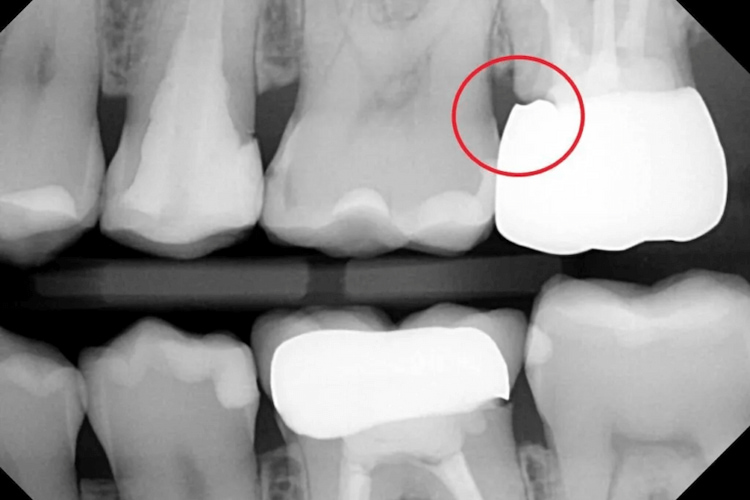

The dentist examines the crown using dental instruments and floss to check for irregular edges. They also observe how the gum tissue reacts during cleaning. X-rays provide a deeper view beneath the crown. They help identify:

- Hidden decay under the crown

- Bone loss or gum changes

- The exact position of the crown margin